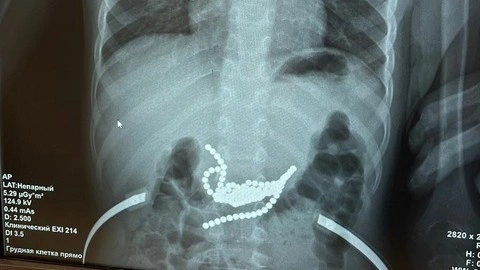

На рентгене врачи увидели десятки небольших круглых шариков. Маленькому пациенту потребовалась очень сложная полостная операция.

«Основная часть магнитов находилась в желудке, другие – в тонкой кишке, поэтому, чтобы извлечь все магниты, пришлось вскрывать просвет и кишки, и желудка. В этом сложность и уникальность операции. Если бы родители обратились в ОДКБ на пару часов позже, могла бы произойти перфорация», - рассказал хирург Антон Штарев.